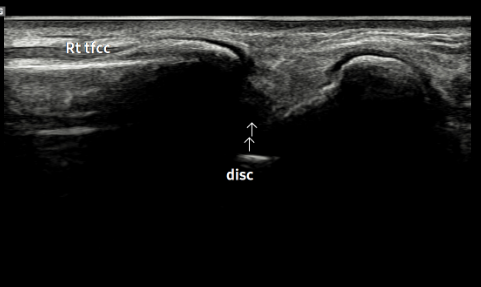

- 치료기간 : 25 . 6 . 9 ~ 25 . 10 .27

- 치료횟수 : 4 사이클(20) 회

치료전

치료 후

힘줄 두께 감소 및 전체적인 파열 부위 축소 & 골극 감소

-> 검사상 파열은 여전히 있지만 운동 이후에도 통증이 크게 없어서 치료 종료 후 3~4주정도 텀 두고 관찰 예정